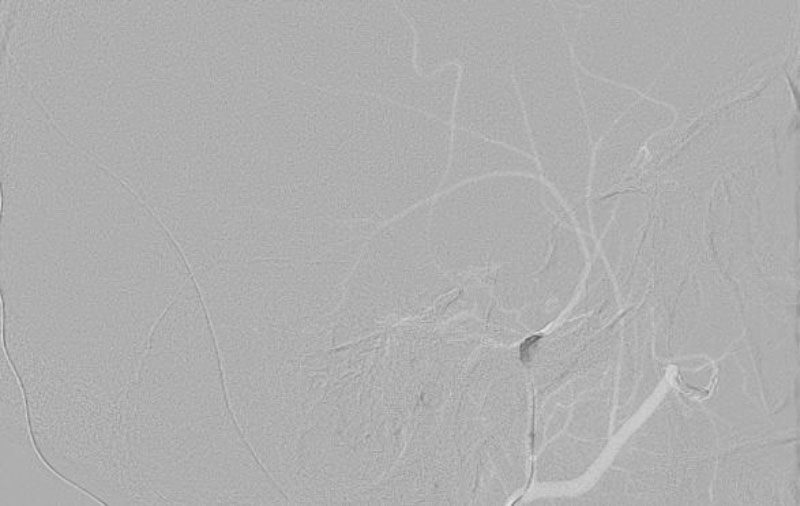

No.1596 手術後